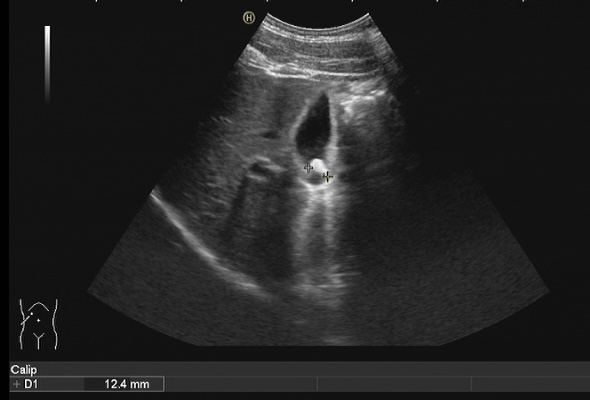

膽結(jié)石診斷方式很多,包括彩超、CT、核磁共振、膽管造影等方式都可以對(duì)膽道結(jié)石進(jìn)行診斷,但是彩超具有無創(chuàng)、無痛、無輻射、廉價(jià)、快速、可重復(fù)性強(qiáng)等優(yōu)點(diǎn),在臨床上被廣泛應(yīng)用作為膽結(jié)石的首選診斷方式。注意做肝膽彩超檢查必須要空腹,才能準(zhǔn)確檢查出膽道結(jié)石哦!

膽囊結(jié)石超聲圖像 | |